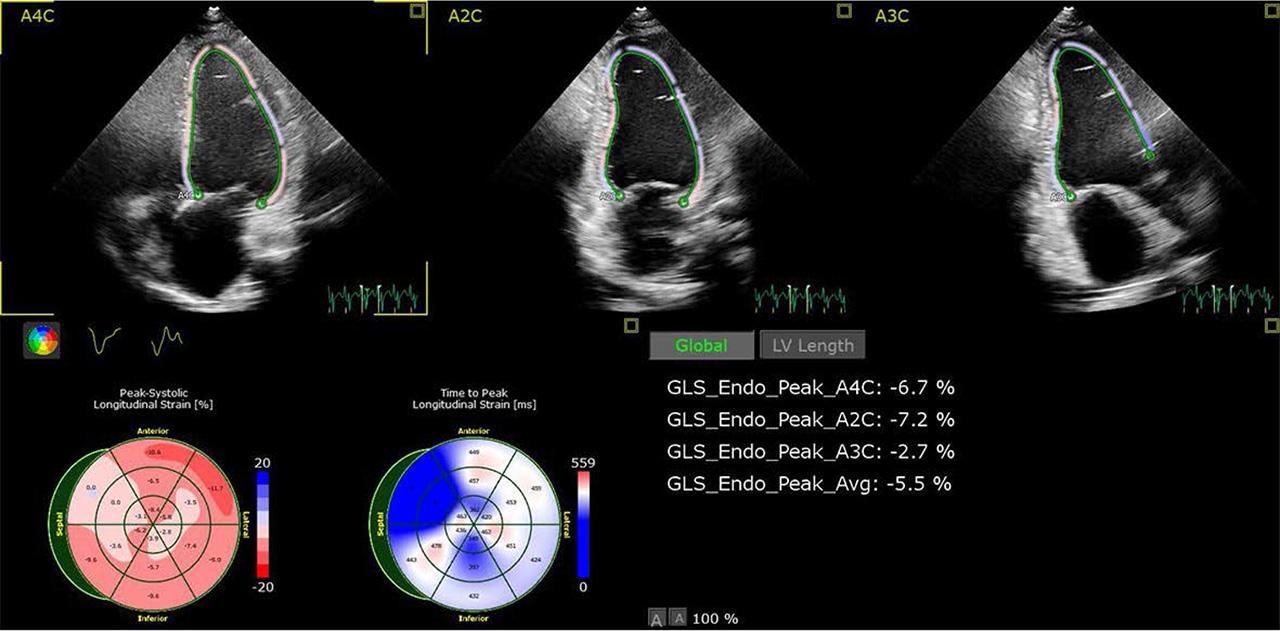

FIGURE 1.